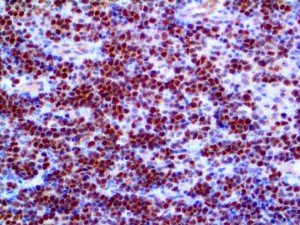

It is the ICU physician who is most likely to witness one of the deadliest manifestations of the abnormal immunological response, the cytokine storm syndrome (CSS). This response is also referred to by some as the cytokine release syndrome (CRS). CSS is characterized by continuous activation and expansion of macrophage and lymphocyte populations, which secrete large amounts of cytokines, causing the cytokine storm. This massive cytokine release is akin to hemophagocytic lymphohistiocytosis (HLH) disease, a syndrome characterized by initial unchecked and persistent activation of cytotoxic T lymphocytes and NK cells.

Clinical and laboratory manifestations of HLH include fever, enlarged liver and/or spleen, neurologic dysfunction, coagulopathy, liver dysfunction, cytopenias (i.e., low levels of erythrocytes, leukocytes, and/or platelets), hypertriglyceridemia, hyperferritinemia, hemophagocytosis, and eventually diminished NK cell activity as the immune system becomes progressively paralyzed. HLH can be familial (primary HLH) or secondary to another disease process (sHLH), such as rheumatic disease, in which it is referred to as macrophage activation syndrome (MAS, characterized by elevated ferritin).